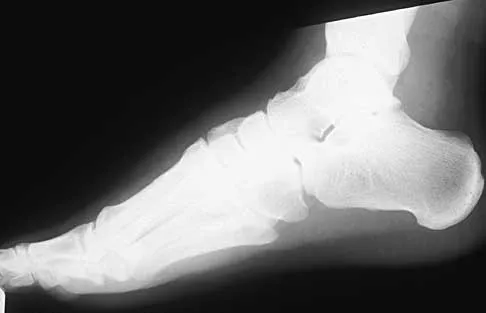

A 45-year-old man who underwent an ankle arthrodesis reports that for the first 6 years he had significant pain relief after the fusion healed. However, he now has increasing pain in the sinus tarsi. AP and lateral radiographs are shown in Figures 8a and 8b. What is the most likely cause of the patient's symptoms?

The patient has a solid ankle fusion radiographically. With a tibiotalar arthrodesis, the adjacent joints (subtalar and transverse tarsal) take additional stress. Over time, progressive degenerative arthritis will occur in these adjacent joints, often necessitating further surgery. Beaty JH (ed): Orthopaedic Knowledge Update 6. Rosemont, IL, American Academy of Orthopaedic Surgeons, 1999, pp 613-631.